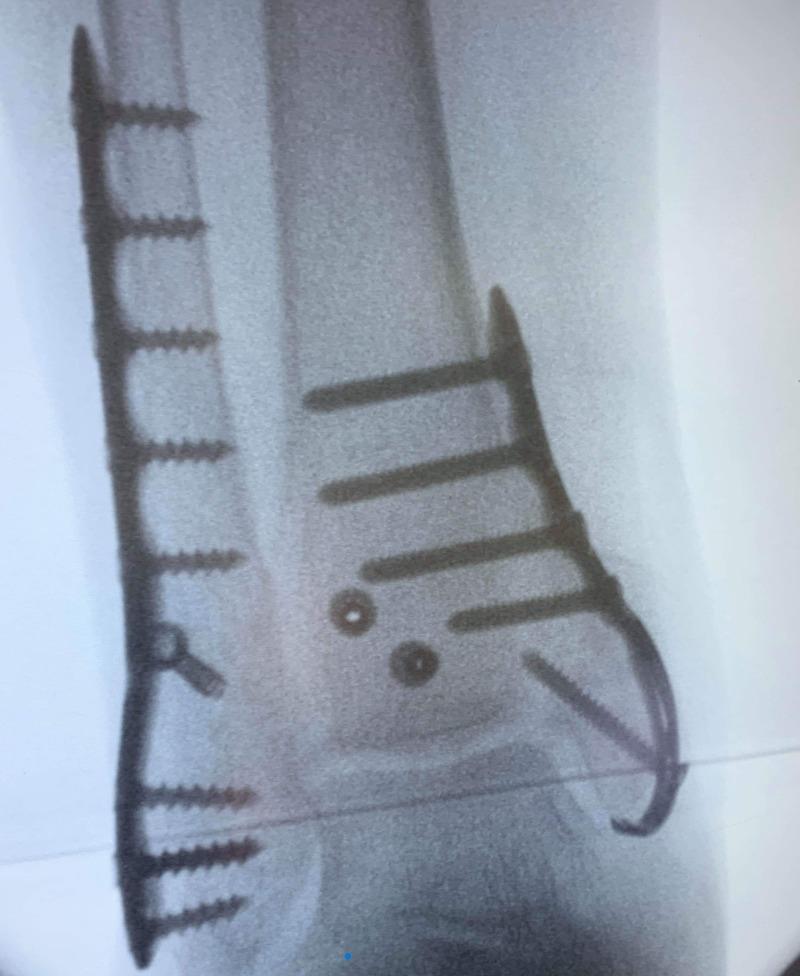

- Distal Femur Plates

- Large Fragment Plates